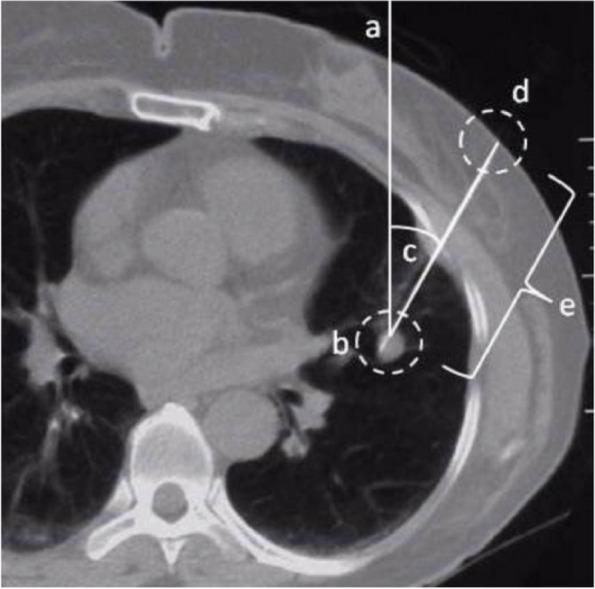

In VATS surgery, precise preoperative localization is particularly crucial when dealing with small-diameter pulmonary nodules located deep within the lung parenchyma. The purpose of this study was to compare the efficacy and safety of laser guidance and freehand hook-wire for CT-guided preoperative localization of pulmonary nodules.

This retrospective study was conducted on 164 patients who received either laser guidance or freehand hook-wire localization prior to Uni-port VATS from September 1st, 2022 to September 30th, 2023 at The First Affiliated Hospital of Soochow University. Patients were divided into laser guidance group and freehand group based on which technology was used. Preoperative localization data from all patients were compiled. The localization success and complication rates associated with the two groups were compared. The risk factors for common complications were analyzed.

The average time of the localization duration in the laser guidance group was shorter than the freehand group (p<0.001), and the average CT scan times in the laser guidance group was less than that in the freehand group (p<0.001). The hook-wire was closer to the nodule in the laser guidance group (p<0.001). After the localization of pulmonary nodules, a CT scan showed 14 cases of minor pneumothorax (22.58%) in the laser guidance group and 21 cases (20.59%) in the freehand group, indicating no statistical difference between the two groups (p=0.763). CT scans in the laser guidance group showed pulmonary minor hemorrhage in 8 cases (12.90%) and 6 cases (5.88%) in the freehand group, indicating no statistically significant difference between the two groups (p=0.119). Three patients (4.84%) in the laser guidance group and six patients (5.88%) in the freehand group had hook-wire dislodgement, showing no statistical difference between the two groups (p=0.776).

The laser guidance localization method possessed a greater precision and less localization duration and CT scan times compared to the freehand method. However, laser guidance group and freehand group do not differ in the appearance of complications such as pulmonary hemorrhage, pneumothorax and hook-wire dislodgement.